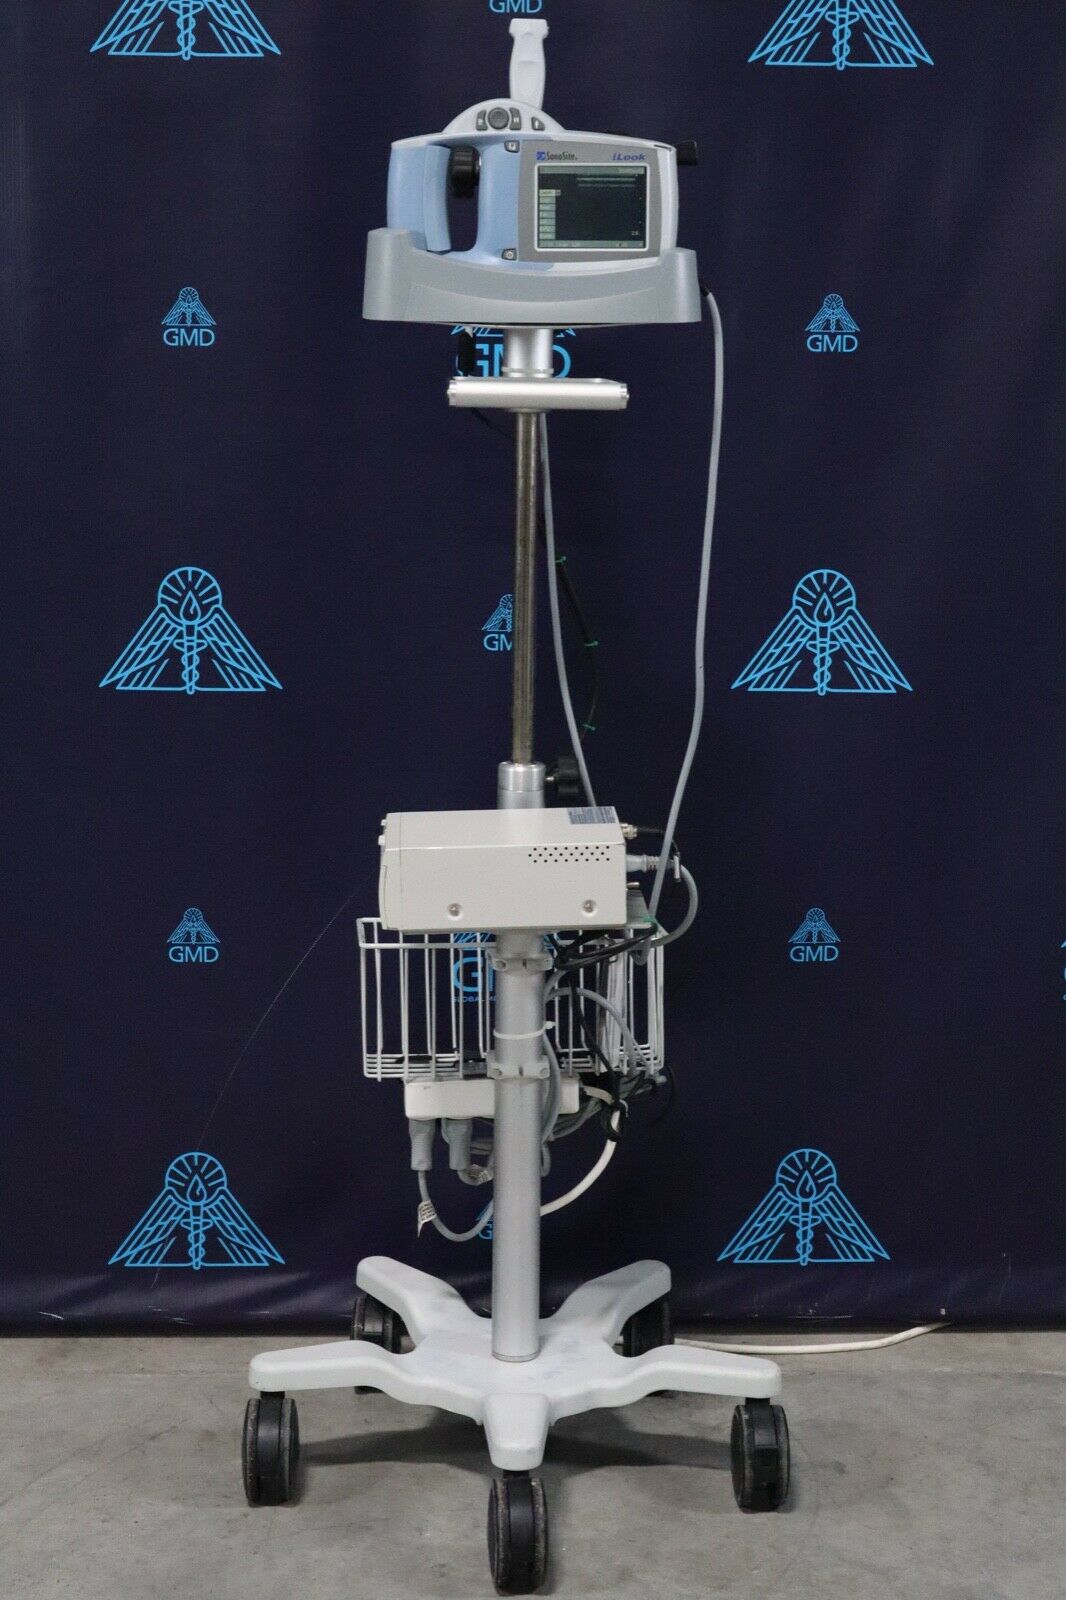

SONOSITE iLOOK PORTABLE ULTRASOUND SYSTEM

Sale price$ 2,950.36